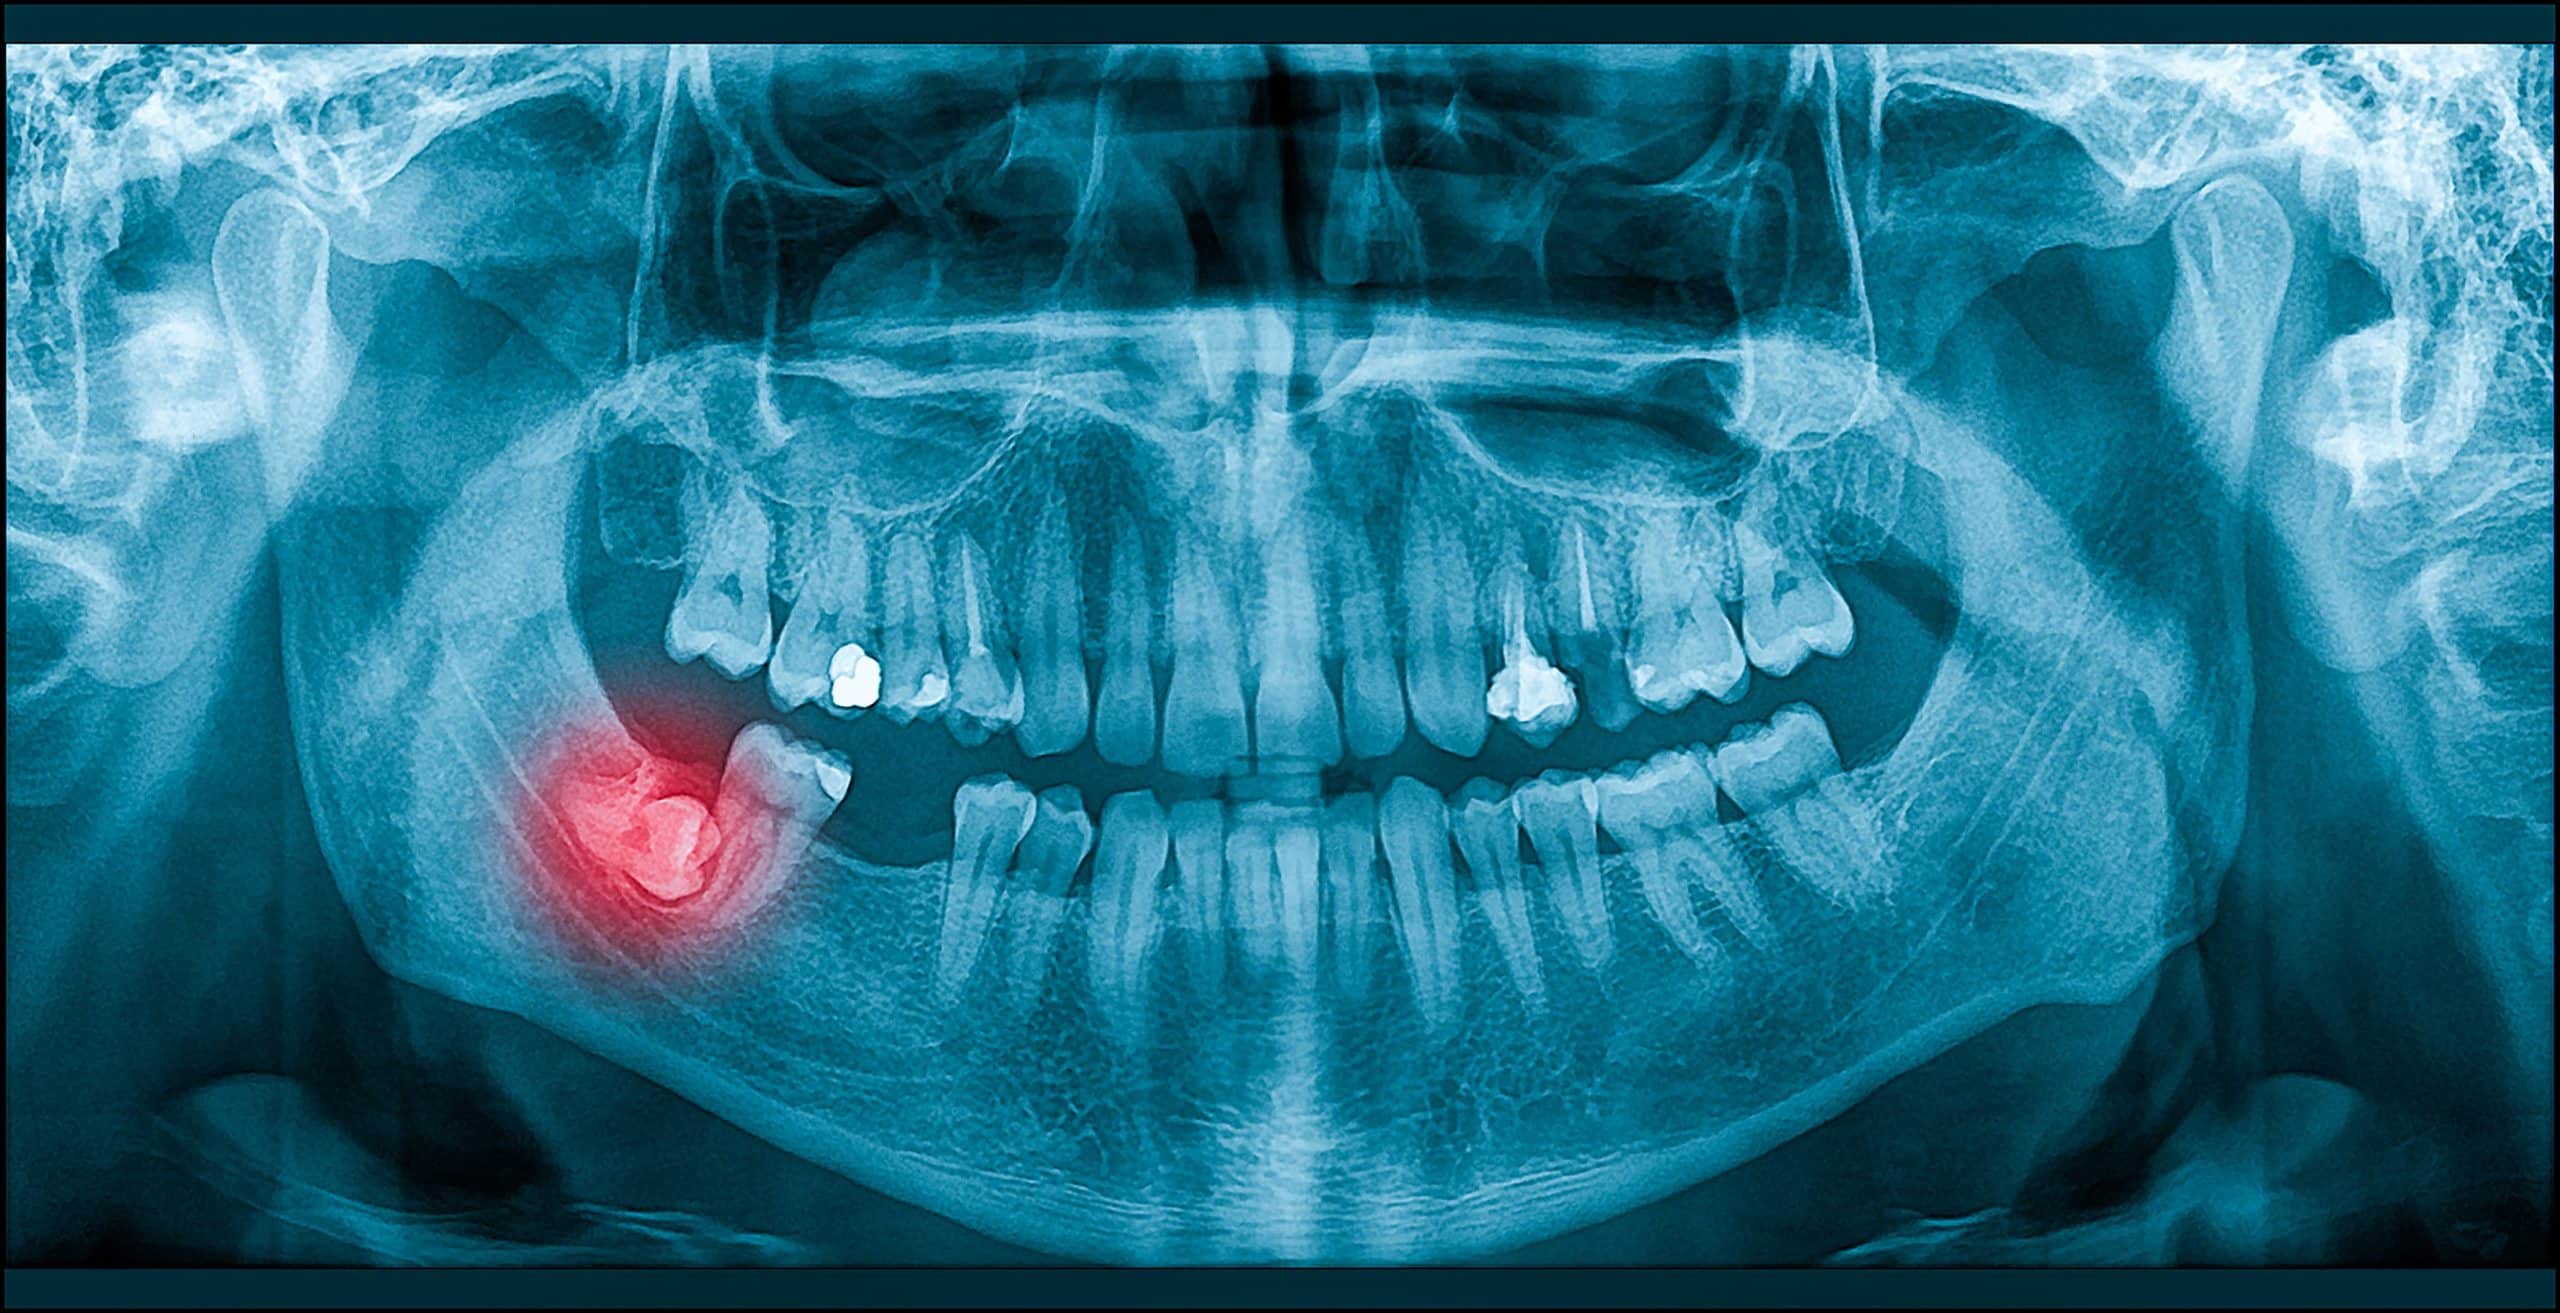

Third molars, also known as wisdom teeth, are the last set of teeth to develop. For many people, the jaw does not have enough space for these teeth to erupt properly. When this happens, the teeth may remain trapped under the gums or push against nearby teeth, which can lead to pain, infection, and long-term complications.

A third molar extraction is recommended when these teeth threaten your oral health. Removal helps prevent crowding, decay, cyst formation, gum infections, or jaw discomfort. At our practice, we take the time to evaluate your condition, explain your options, and deliver treatment with the highest level of precision.

Impaction occurs when the wisdom teeth cannot fully break through the gums. Common symptoms include:

At Exquisite Dental Implant Center, we use advanced digital imaging to determine whether your wisdom teeth are impacted and to plan safe and effective removal.

Impacted third molars remain partially or fully stuck beneath the gums, often positioned at an angle. Erupted wisdom teeth have broken through the gums, but may still cause problems if there is not enough space. Our evaluation helps determine whether surgical wisdom tooth extraction is needed based on your specific anatomy.